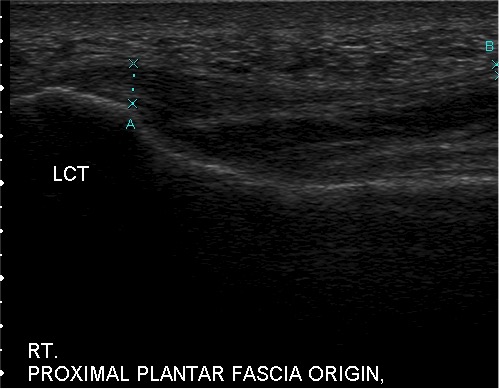

With the advent of musculoskeletal ultrasound, we can effectively diagnose plantar fasciopathy with a high degree of specificity and individually design treatment plans for the level of pathology present in the patient.10 High-resolution sonography allows the practitioner to grade the level of degeneration. Then one should tailor treatment to the level of tissue degradation. For example, sonograms can clearly reflect different levels of severity, requiring different treatment approaches ideally for optimal results. Those practitioners who do not assess the level of tissue degeneration with high-resolution diagnostic ultrasound are pretty much forced to use a cookie-cutter approach as they do not really know what they are treating. Visualization is everything from diagnosis to surgical technique.

The study by Monto and colleagues illustrates the power of regenerative medicine for a degenerative condition. This is why fewer EPFs are necessary at this time. By implementing amniotic tissue allograft (stem cells), I have found more profound effects in treating plantar fasciopathy. While I reserve EPF for patients in a IVB or IVC category on the Barrett Plantar Fasciopathy Ultrasound Grading System (see left), I still recommend intervening with ultrasound-guided partial plantar fasciotomy with amniotic tissue allograft, even for those patients who are likely to need an EPF.